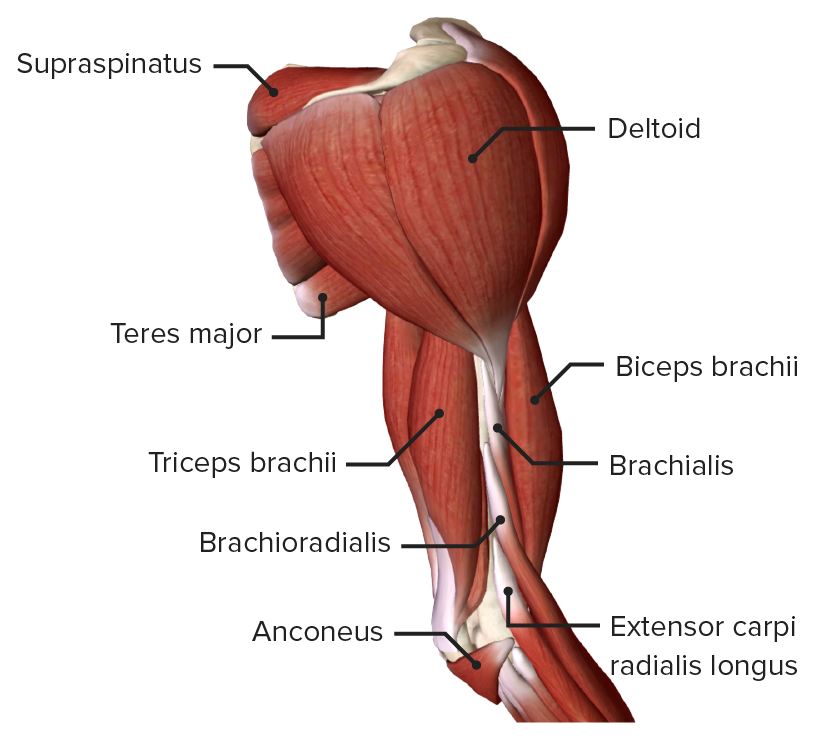

Анатомия и функции мышцы brachioradialis